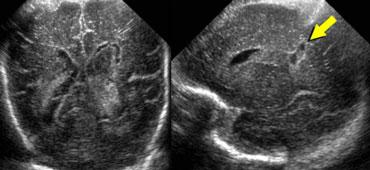

Xuất huyết nội sọ độ 4

Ban đầu, các xuất huyết độ 4 này được cho là do chảy máu dưới màng nội tủy lan vào nhu mô não lân cận.

Tuy nhiên, ngày nay hầu hết các chuyên gia cho rằng các xuất huyết độ 4 này là nhồi máu xuất huyết tĩnh mạch, là hậu quả của sự chèn ép dòng chảy tĩnh mạch bởi xuất huyết dưới màng nội tủy.

Hình bên trái là xuất huyết độ 4.

Có một ổ chảy máu dưới màng nội tủy lớn kèm theo một vùng tăng âm rộng trong nhu mô não ở phía bên của não thất.

Đây có thể là hậu quả của nhồi máu tĩnh mạch.

Các ổ nhồi máu tĩnh mạch này thoái triển với sự hình thành nang.

Các nang này có thể hợp nhất với não thất bên, cuối cùng dẫn đến hình thành nang não lỗ.

Hình bên trái là một bệnh nhân khác với xuất huyết độ 4 ở giai đoạn muộn hơn với sự hình thành nang lan rộng.